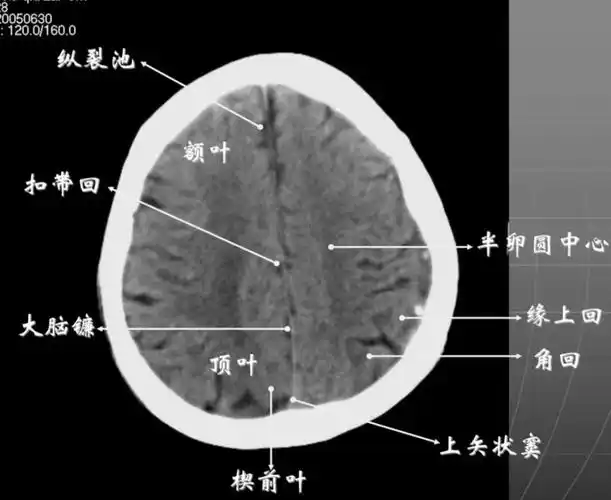

8大脑皮质上部层面(半卵圆区上部层面)已近颅顶,大脑镰清晰可见,其旁